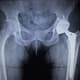

Total hip arthroplasty (THA) is a common procedure performed primarily on older patients suffering from osteoarthritis or osteonecrosis, painful conditions that severely limit mobility and lifestyle choices. But some surgeons have been hesitant to perform THAs on patients with HIV or AIDS due to concerns about complications, including higher risk of infection, need for revision surgery, and increased length of hospital stay.

Using data from the National Inpatient Sample covering 2016-2019, UTSW researchers identified 504 HIV-positive patients who underwent THAs and compared their postoperative complications to a cohort of 493 HIV-negative patients. Their findings, published in the Journal of Clinical Orthopaedics and Trauma, showed that postoperative complications such as pneumonia, periprosthetic infection, wound dehiscence (reopening), and superficial and deep surgical site infection were not significantly different between the HIV-positive and HIV-negative groups. Blood transfusion rates also were lower among the HIV-positive patients.